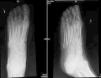

En la exploración cutánea se apreciaba una úlcera con exudado amarillento, de bordes indurados con piel atrófica adyacente. El análisis de sangre no mostraba leucocitosis ni un aumento de proteína C reactiva. Se realizó una biopsia cutánea amplia del borde y fondo de la úlcera, cuyo estudio histológico mostró una dermis con fibrosis colágena y la presencia de signos de vasculopatía, sin atipia celular, todo ello compatible con radiodermitis, descartando procesos neoplásicos. El cultivo microbiológico del exudado evidenció la presencia de Vibrio alginolyticus (V. alginolyticus) (fig. 1A). Se inició tratamiento con ciprofloxacino oral, según antibiograma, a pesar de lo cual la evolución fue tórpida, con formación de un absceso cutáneo (fig. 1B) y desarrollo de osteomielitis (fig. 2), que requirió ingreso hospitalario. Se realizó desbridamiento quirúrgico, a pesar de que en el cultivo del absceso no creció ningún microorganismo, y se pautó antibioterapia endovenosa con doxiciclina y ceftriaxona durante 10 días, presentando una buena evolución con resolución de la úlcera al cabo de 3 meses.